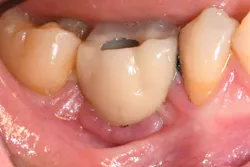

If the occlusal forces delivered to the implant-abutment-crown complex exceed the screw’s clamping ability, this may result in either its loosening (figures 1a and 1b) or, in more severe situations, fracturing of the screw (figures 2a–2c). Clinicians often indite the occlusion as being the primary culprit for the problem; however, in a number of instances, this may not be the case. The cause of screw loosening could also be due to using aftermarket parts, which do not have the precise fit of those made by the manufacturer of the implant.7